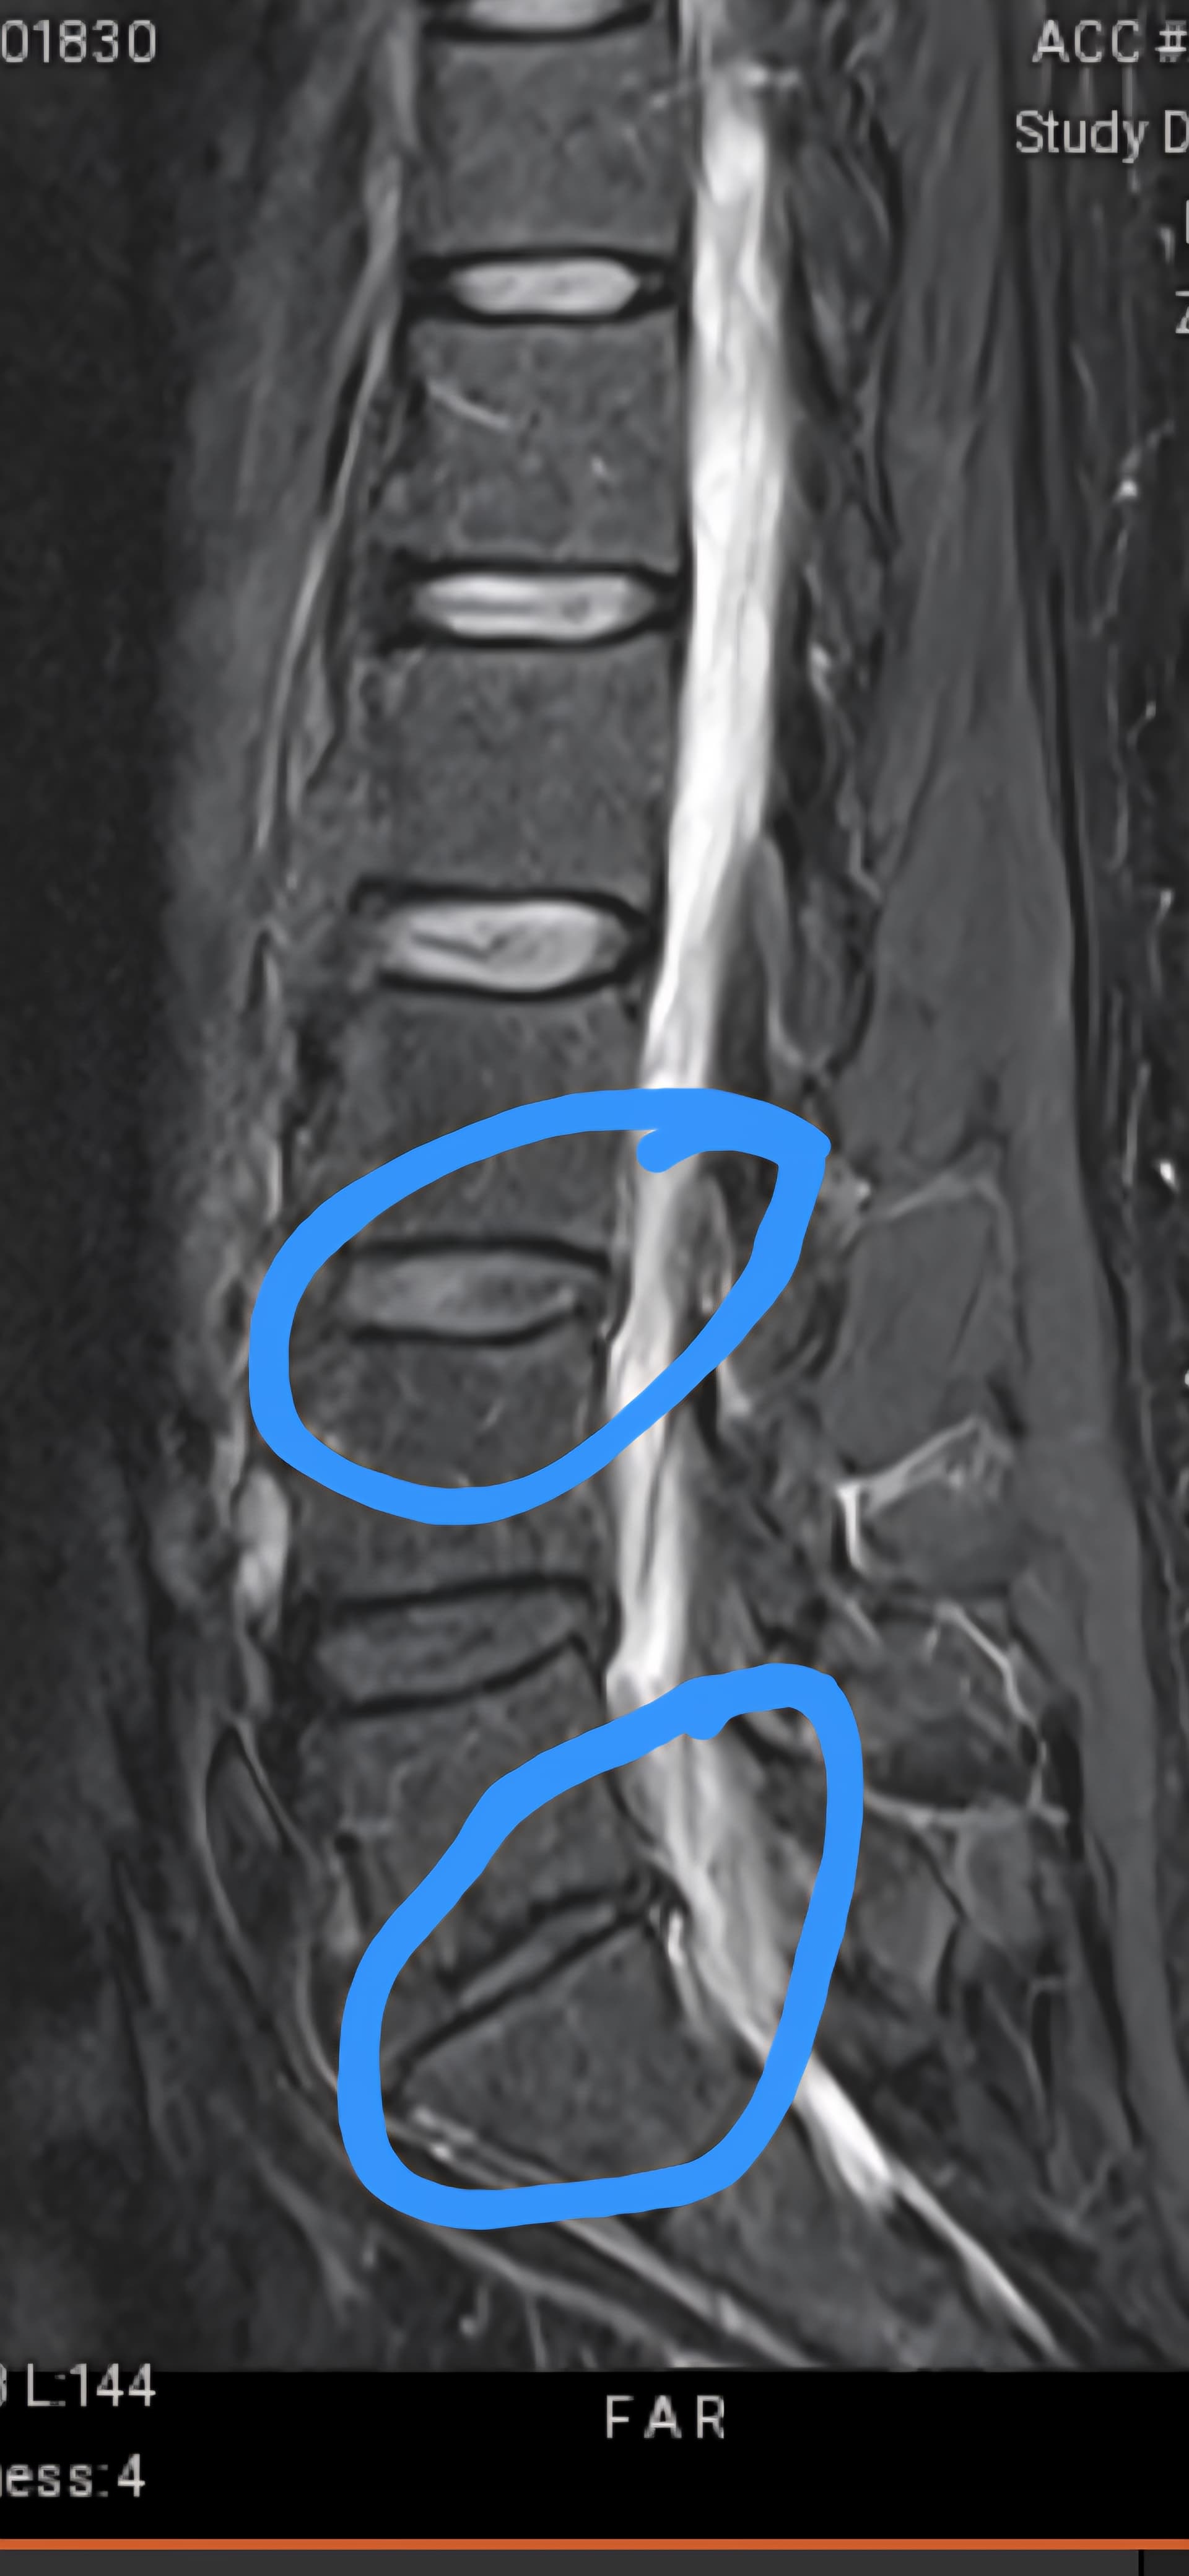

Anyways, finally had my mri on Thursday. I have a follow up with the specialist tomorrow on next steps, although I’m pretty certain that a back fusion is in my near future.